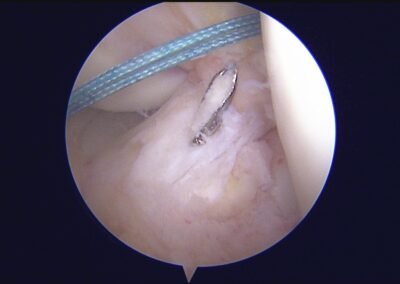

GalleryShoulder rotator cuff repair Meniscus root repair Meniscus repair Bankart repair for recurrent shoulder dislocation ACL reconstruction Machines Instruments